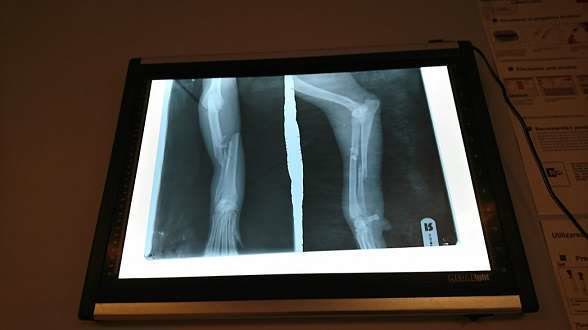

It is incredible how some people think that if they go to church or give a dime to a beggar they did such a great deed and they are forgiven for every sin, even more, they think they have a special place in Heaven. We are very upset because day by day we are under assault by messages one more painful than the other, and we are a nervous wreck, we just can’t face all these abandonments, atrocities and idifference. We rescued mother with babies, they are all grown up now, sterilized and we can’t find responsible adoption for them. Day by day we hope to find loving homes for them for the rest of their lives. But our problems are harder and harder; a lot of dogs which we have for 12-17-20 YEARS are starting to have problems, they need special care, many we saved remained paralyzed and can’t walk anymore, but we are home, and we love them for the rest of their lives. We could go on with our old cats who can’t resist in the enclosure and need warmth and care so we moved them inside with us. That is why we can’t understand how one can pass day by day by a dog who is lying in a ditch and can’t move. We know that she stayed there for 5 days, but in reality only she knows for how long and how she suffered. When we first found out about her we trembled, it was already dark outside and it was going to be a nightmare for her, alone and desperate with no one to care for her. We can’t even imagine the suffering she would’ve died in if we wouldn’t have saved her and rushed her to the clinic. She has 2 fractured legs, but is now operated and in proper care and when she will be released, we will be her home. We know the holidays are coming and everyone has great expenses but we hope you will not leave us alone to cover the costs, costs that are not small, in adition, we still have debts from other cases, we still haven’t paid. Thank you all!

UPDATE:Lucy was operated on both legs and to our great joy she started walking again!